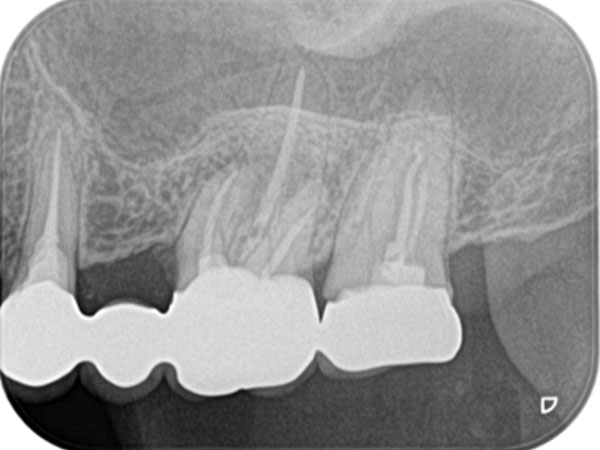

下の写真をご覧ください。歯の中に見える黒い部分が「根管」です。根管の形は複雑で、患者さんひとりひとりによって異なります。しかも細いところは直径1mmもありません。こんなに狭くて複雑な根管から、感染部位を正確に取り除くというのは困難を極めます。

複雑な根管を治療するには、事前の画像診断で根管の形状を可視化することが重要です。多くの歯科医院では、画像診断に「2次元」のレントゲンが用いられますが、レントゲンでは初期の患部を見つけにくい上に、根管の複雑な形状をしっかり可視化するほどの力はありません。

そこで、当院では3次元で撮影ができる「CT」を利用します。CTはあごの骨の中を立体的に可視化するので、レントゲンには写らない患部の様子までがしっかりわかります。日本国内の歯科医院での、CTの普及率は5〜10%程度と言われています。